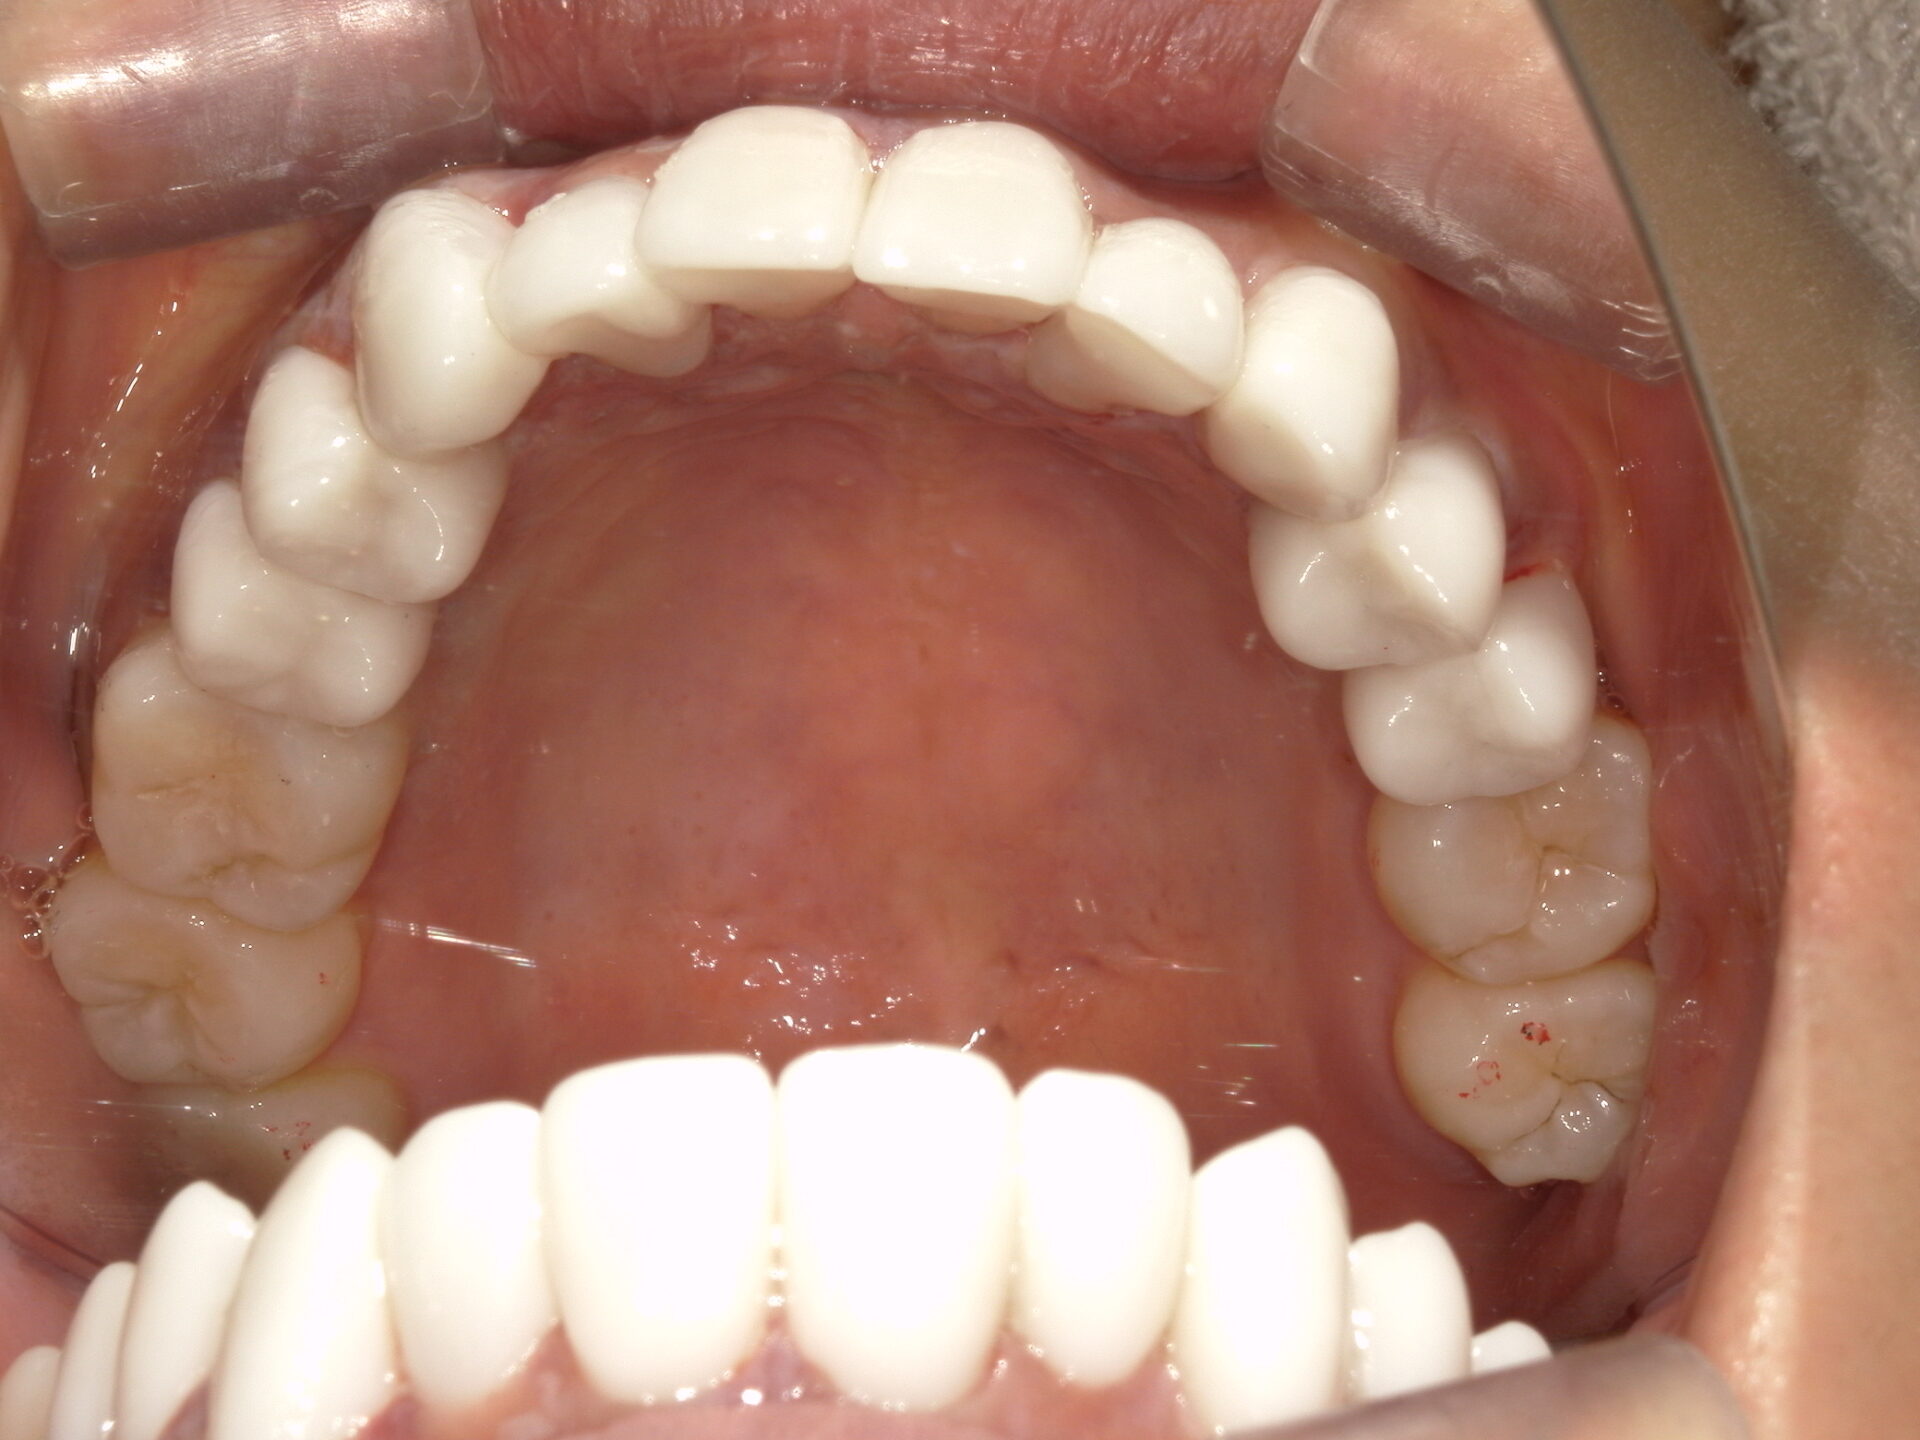

after

患者さんの年齢 20代 女性 症状 見た目が良くなりたい 治療内容 マウスピース矯正治療 費用 90万(税抜) 治療期間・回数 治療期間2年半、通院回数20回 メリット スマイルラインが綺麗 デメリット・リスク 期間がかかることがある 患者さまの声 見た目が綺麗になった - マウスピース矯正